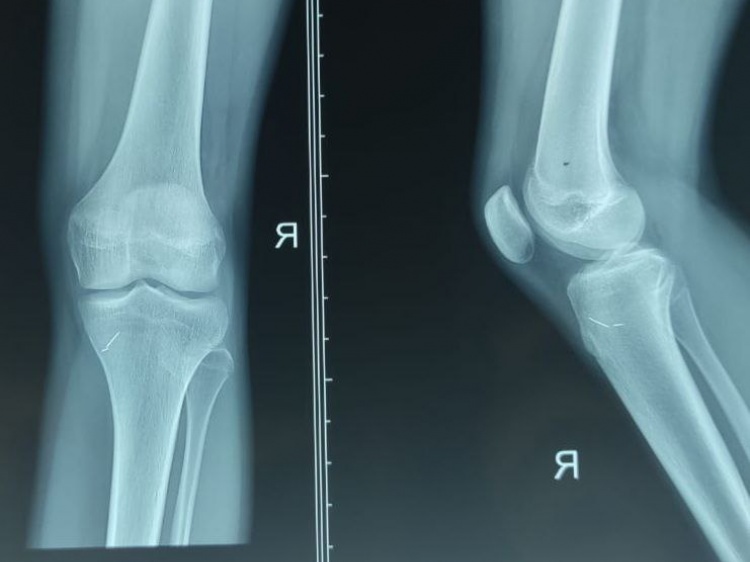

В Волгоградской области травматологи-ортопеды извлекли обломки швейных игл из коленного сустава девочки, которые находились в теле 4 года.

Как рассказали Волжский.ру в Волгоградской областной детской клинической больнице, в 10 лет девочка случайно упала на игольницу, но не сказала ничего родителям, так как боялась реакции и возможной операции. Все эти годы девочка жила с болью, которая мешала нормально двигаться. Когда боль стала невыносимой, она перестала наступать на ногу, что и заметили родители. Из районной больницы семью направили в областную клинику, где провели всестороннее обследование и успешную операцию.

Из-за длительного нахождения инородных предметов в суставе развился воспалительный процесс, что и привело к ограничению движения. Теперь девочке потребуется восстановительное лечение.